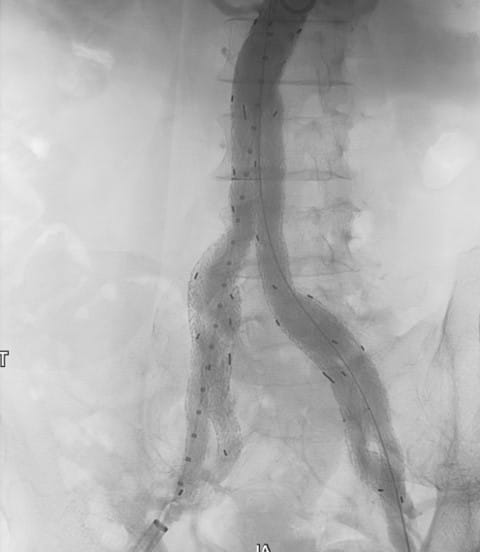

A 76-year-old male presented to UPMC for evaluation of aortoiliac aneurysm disease. His past medical history is also significant for mild emphysema, hyperlipidemia, lung and prostate cancer, and he has no family history of aneurysmal disease or connective tissue disorder. He is without symptoms of cardiac ischemia or peripheral claudication. His preoperative CT scan demonstrated the presence of a small infrarenal abdominal aortic aneurysm measuring 4.8cm, and bilateral large common iliac artery aneurysms, measuring 4cm and 3.8cm on the right and left, respectively. The internal iliac arteries were patent bilaterally (Figure 1 and 2). He underwent endovascular repair of his abdominal aortic aneurysm with placement of bilateral iliac branch endoprostheses (Gore Medical, Flagstaff AZ) for his bilateral common iliac artery aneurysms via percutaneous bilateral common femoral artery access (Figures 3-6). The patient tolerated the procedure well and was discharged on post-operative day two.

Figure 5: Positioning of the right iliac branch endoprosthesis. The up-and-over wire and the main body wire are free of wire wrap. The left iliac branch endoprosthesis is fully deployed.

Figure 6: Preparation for deployment of GORE Excluder for abdominal aortic aneurysm. Both iliac branch endoprostheses are fully deployed.